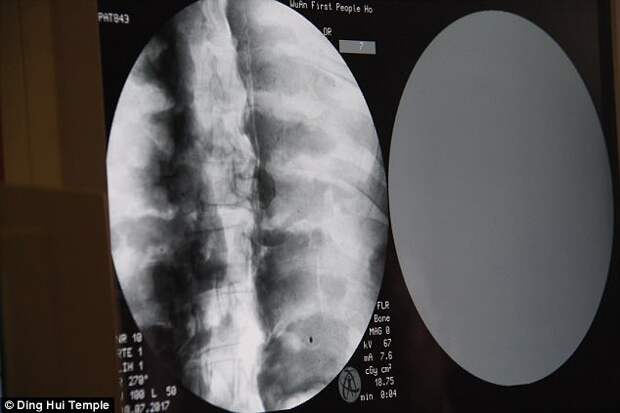

Это показала недавно проведенная компьютерная томография

Компьютерная томография прошла 8 июля. Люди были шокированы, когда врачи сказали, что у Цы Сяня в идеальном состоянии сохранился скелет и мозг. «Мы можем видеть, что его кости такие же здоровые, как у нормального человека. Верхняя челюсть, верхние зубы, ребра, позвоночник и все суставы отлично сохранились. Это невероятно», — сказал доктор Ву Йонтин (Wu Yongqing).